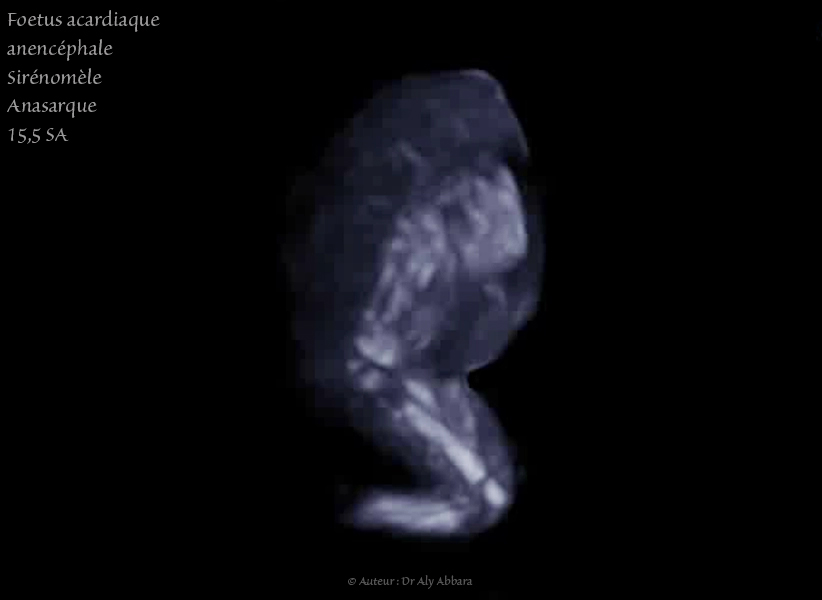

Grossesse gémellaire monochoriale bi-amniotique à 15,5 SA avec un jumeau polymalformé :

Anencéphalie, amélie bilatérale supérieure, sirénomélie, oedème généralisé - Rotation axiale, échelle de gris

• Foetus acardiaque : pas structures cardiaques (holoacardius), mais la présence d'une vascularisation provenant de l'autre jumeau normal (jumeau pompe) par le cordon ombilical.

Anencéphale (acrânie - acranius) : absence de structures céphaliques identifiables.

• Amélie des membres supérieurs (absence des deux extrémités supérieures)

• Sirénomélie : un seul membre inférieur comportant deux segments : supérieur avec un fémur, et inférieur contenant deux os longs, mais apodie (absence de pied). Ce membre inférieur est parfois animé par certains mouvements de type flexion - déflexion très réduites.

• Probable vessie (entourée par les deux artères ombilicales) ; une structure digestive liquidienne ; un segment désorganisé du rachis ; quelques côtes incomplètes.

• Un œdème fœtale généralisé sous-cutané majeur enveloppant ce fœtus acardiaque.

• L'estimation du poids de ce jumeau acardiaque est égale 7,7 grammes pour une longueur de 3,3 cm, contre 118 grammes + 10 % pour le jumeau pompe (donneur normal).